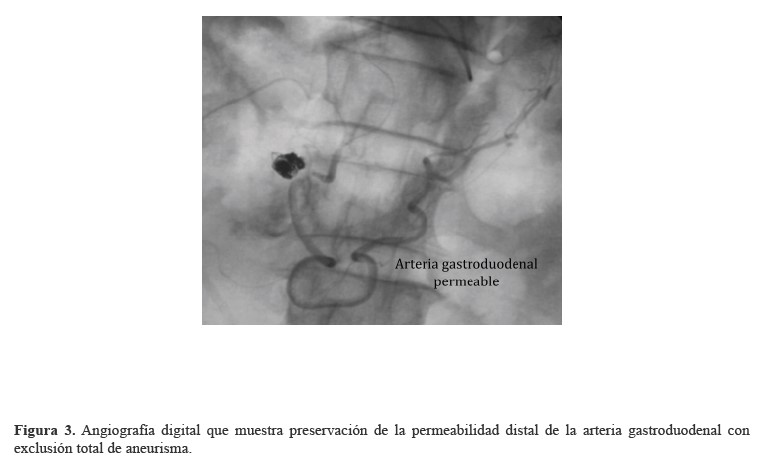

Se decidió intervenir al paciente con manejo endovascular con coils, realizando una punción en la arteria braquial derecha. Posteriormente, se ejecuta aortograma y se identifica el tronco celíaco. A continuación, se efectúa cateterismo supraselectivo de la arteria gastroduodenal y se realiza angiografía, que muestra sangrado activo de aneurisma sacular de la arteria gastroduodenal, con extravasación del medio de contraste. Inmediatamente, se cateteriza el aneurisma y se emboliza con coils; así, se logra el manejo del sangrado y una adecuada tolerancia del paciente al procedimiento. En control angiográfico, se observó exclusión total de AAG con flujo escaso distal y, en aortograma abdominal, se identificó aorta abdominal normal (Figuras1-4).

Figura 3. Angiografía digital que muestra preservación de la permeabilidad distal de la arteria gastroduodenal con exclusión total de aneurisma.